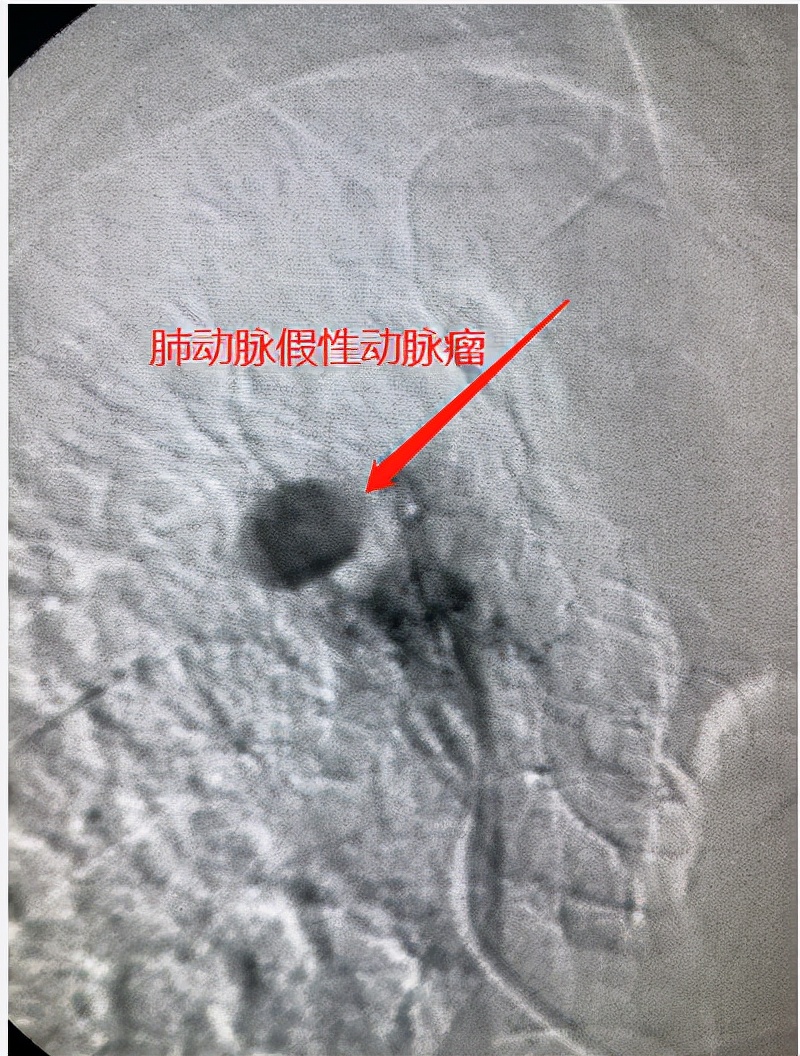

患者于10:37時急診CTA并行急診介入手術(shù),CTA影像示有一肺動脈假性動脈瘤(PAPA),瘤體隨時有破裂大出血的危險。12:33分,DSA影像示PAPA 術(shù)中再次破裂,患者再次大咯血,出血量約500ml。介入醫(yī)生從容栓塞,即刻止血!

肺動脈假性動脈瘤好發(fā)于肺內(nèi)病變空洞內(nèi)(肺癌空洞、結(jié)核空洞、肺膿腫空洞、霉菌空洞等等),診斷金標(biāo)準(zhǔn)為MDCTA。癥狀一般為陣發(fā)性大咯血,一旦發(fā)生,死亡率極高,死亡原因多為窒息死亡。內(nèi)科用藥止血基本無效。介入栓塞治療肺動脈假性動脈瘤,可即刻止血,創(chuàng)傷小,傷口只有一個針眼,瘤腔封閉徹底,并發(fā)癥少,療效好,是極有效的治療方案!!!